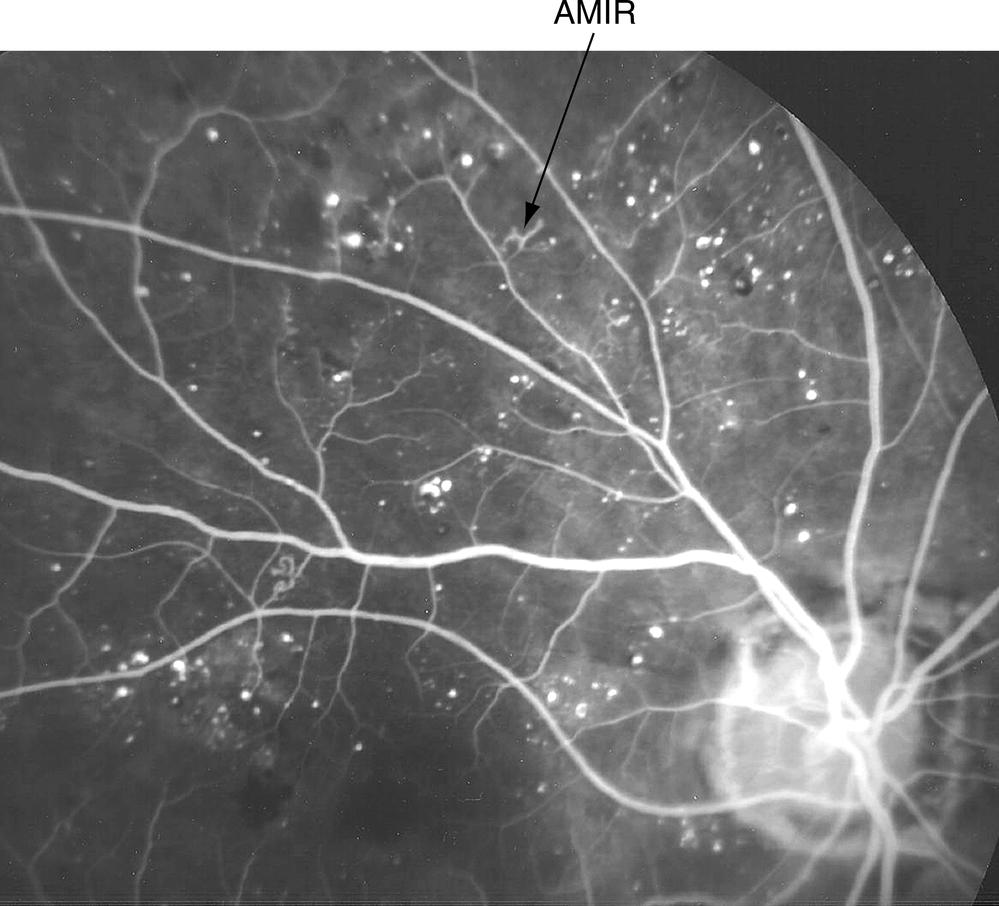

• AMIR dans un ou plusieurs quadrants (fig. 5-9).

Figure 5-9

Anomalies microvasculaires intrarétiniennes (AMIR) dans le cadre d'une RDNP. Angiographie à la fluorescéine montrant des micro-anévrismes, des zones de non-perfusion et un remodelage capillaire intrarétinien (flèche).

(Remerciements au Dr Hermann D. Schubert.)